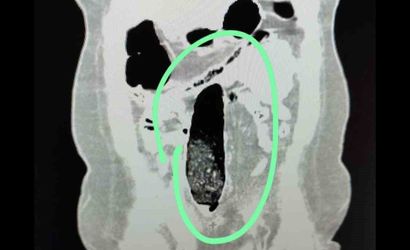

Yapılan kontrollerde şüpheli şahısların iç beden muayeneleri gerçekleştirilmiş; şahısların vücutlarının doğal boşlukları ve bağırsaklarında uyuşturucu madde bulunduğu belirlenmiştir. Tıbbi müdahale ile söz konusu maddelerin çıkarılması sağlanmıştır.

Tıbbi müdahale sonucu, F.V. isimli kadın şahıstan üç parça halinde toplam 397,78 gram metamfetamin ele geçirilmiş; S.İ. isimli erkek şahıstan ise 24 adet sentetik hap ile üç parça halinde toplam 167,68 gram metamfetamin elde edilmiştir.